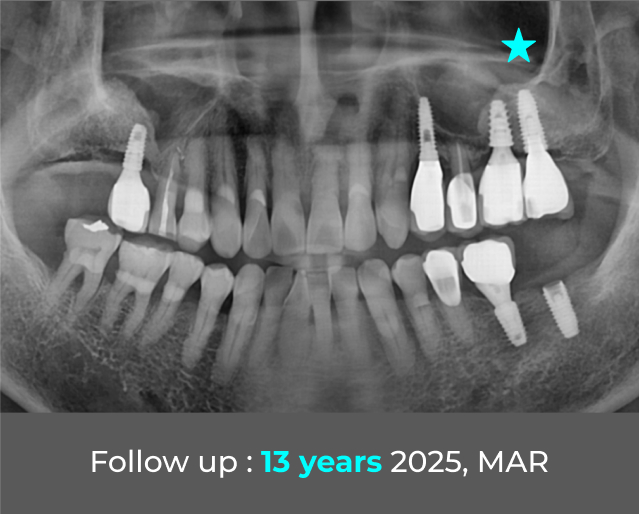

13+ Years LONG-TERM Case Report